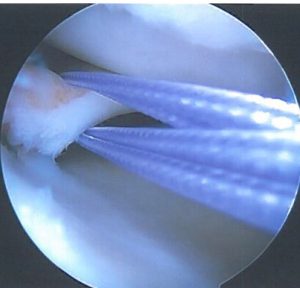

Η αρθροσκοπική θεραπεία έσω και έξω μηνίσκου είναι μια μοντέρνα μέθοδος όπου με δύο ή τρείς μικρές οπές στο έσω και έξω μεσάρθριο διάστημα με τη βοήθεια αρθροσκοπίου και εξειδικευμένων εργαλείων γίνεται αντιμετώπιση και θεραπεία της ρήξης του έσω και έξω μηνίσκου.

Σε περιφερικές ρήξεις που υπάρχει σχετική αιμάτωση και αγγείωση στον μηνίσκο κυρίως σε νέα άτομα κάτω των 35-40 ετών γίνεται προσπάθεια συρραφής του μηνίσκου.

Στις πλείστες όμως περιπτώσεις που η ρήξη του μηνίσκου είναι κεντρικότερα, στις περιοχές αυτές η αιμάτωση είναι ελλιπής και τότε αντιμετωπίζεται με μερική μηνισκεκτομή δηλαδή αφαιρείται τμήμα του ρηθέντος μηνίσκου με προσπάθεια να διατηρηθεί το μεγαλύτερο μέρος του μηνίσκου ακέραιο.